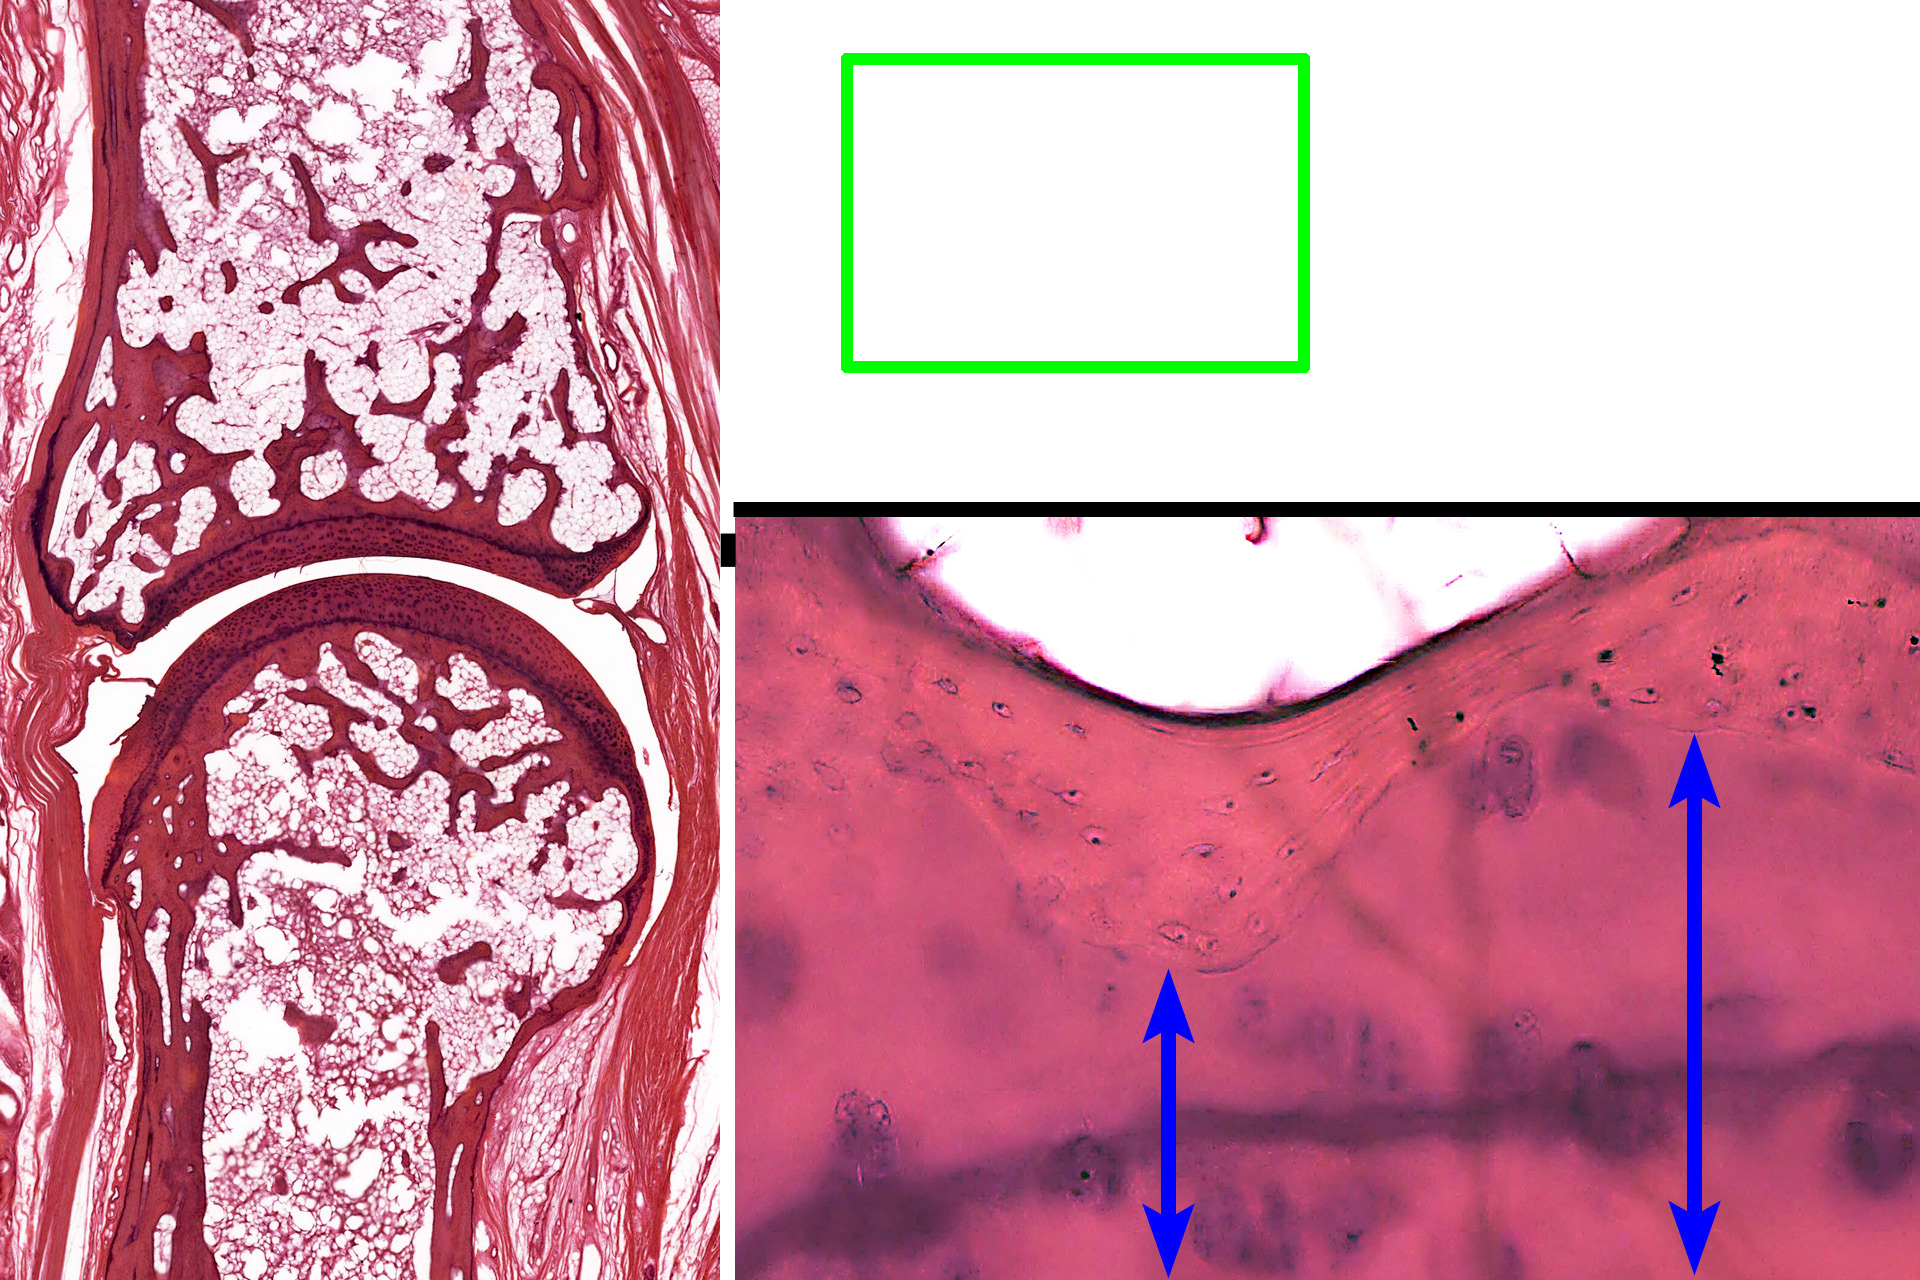

The ends of long bones are covered by articular cartilage, formed of hyaline cartilage, providing a smooth, glassy surface that allows the ends of the bones to move easily on each other. This type of articulation is called a synovial joint. Articular cartilages, which are not covered by periosteum, are separated by a fluid-filled synovial space. A thin layer of compact bone lies beneath the cartilage. 10x, 800x